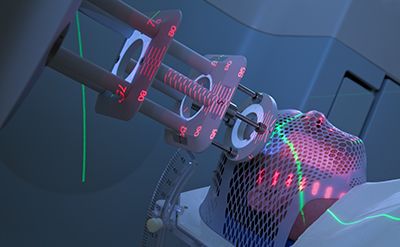

In this learning module for oncology trainees, oncologists and healthcare clinicians interested in oncology, Dr Sophie Raby discusses advances in radiotherapy techniques. Key learning points include the indications for the use of each approach and their practical applicability within the context of the NHS.

● Understand the usefulness and prevalence of radiotherapy in cancer management

● Learn about the types of stereotactic radiotherapy, challenges involved, and indications for these procedures

● Consider the clinical utility of high-energy proton radiotherapy and patient eligibility for this treatment

● Review the clinical utility of a magnetic resonance linear accelerator (MR LINAC) in planning radiotherapy treatment

● Read about how 4D imaging is used in the planning and delivery of radiotherapy

● Refer to the clinical practice of deep inspiration breath hold for patients receiving radiotherapy to minimise cardiac exposure to radiation magnetic resonance linear accelerator (MR LINAC) in planning radiotherapy treatment

Roentgen discovered X-rays in 1895, and for 50 years from 1907, radiation was used to treat ringworm

(Image credit: ZU_09/DigitalVision Vectors/Getty Images)

The last few decades have seen the evolution of conformal external beam radiotherapy (CRT), which uses computed tomographic (CT) images to precisely delineate a target, with X-ray beams from different directions targeting a tumour. Prior to this, radiotherapy beams were delivered using minimal image guidance as simple square or rectangular fields.

Conformal radiation therapy (CRT)

(Image credit: JazzIRT/Getty Images)

Intensity-modulated radiotherapy (IMRT) is an extension of CRT, in which individual beams can be modified to produce doses of varying intensity, sculpting and shaping the beam to produce a concave shape. This reduces the dose and, consequently, the toxicity, to nearby normal tissues.

Intensity-modulated radiotherapy (IMRT)

(Image credit: Mark Kostich/Getty Images)

Unlike IMRT, which uses multiple different beams of different intensities to produce an inhomogeneous dose distribution, volumetric modulated arc therapy (VMAT) can deliver dose continuously as the gantry of the linear accelerator (LINAC) rotates around the patient, hence reducing treatment time and minimising the overall dose. It is being increasingly used for everyday radiotherapy treatment and is especially useful when a tumour is next to a critical organ at risk.

Volumetric modulated arc therapy (VMAT)

(Image credit: Mark Kostich/Getty Images)

Stereotactic radiotherapy is the precise delivery of a focused high dose per fraction irradiation to small targets using advanced image guidance, delivery apparatus and patient immobilisation systems.

It has seen a rapid increase in use among patients with a limited burden of metastatic disease (often referred to as oligo-metastatic disease). Thanks to the improvements in non-curative systemic therapies, there is a growing population of patients living with active metastatic malignancy.